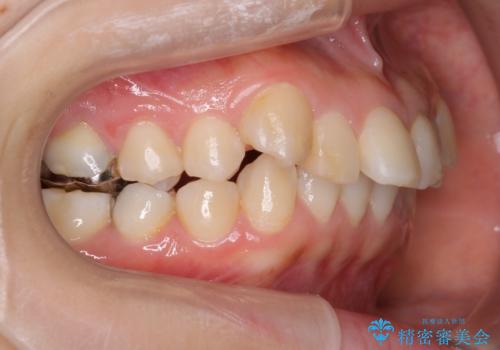

見た目だけではなくかみ合わせも良くなったと満足して頂きました。

治療後は見た目だけでなく、噛みやすくなったと満足していただけました。